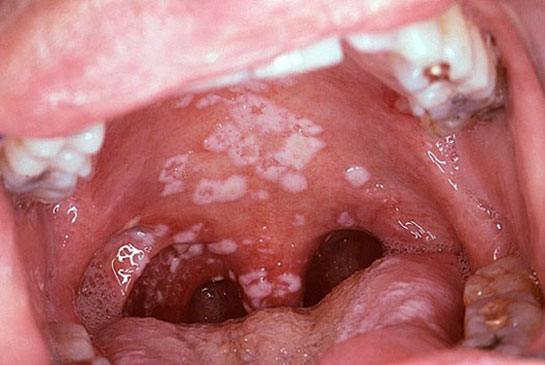

Rahimde Yara Yakılmasının Belirtileri ve Tedavisi Rahimde yara yakılması, tıbbi literatürde "rahim serviksinde (ağız) veya endometriumda (rahim içi) lezyonların yok edilmesi" anlamına gelir. Bu işlem genellikle anormal hücrelerin veya rahim ağzı kanserine zemin hazırlayan hücre değişikliklerinin tedavisinde uygulanır. Rahimde yara yakılması, cerrahi bir prosedür olup, genellikle lazer, kriyoterapi veya elektrokoterizasyon gibi yöntemlerle gerçekleştirilir. Rahimde Yara Yakılmasının Belirtileri Yara yakılması sonrasında hastalarda görülebilecek bazı belirtiler şunlardır:

Bu belirtiler genellikle geçicidir, ancak bazı durumlarda daha ciddi sorunların belirtisi de olabilir. Dolayısıyla, belirtiler uzun sürerse veya şiddetlenirse bir sağlık profesyoneline başvurmak önemlidir. Rahimde Yara Yakılma Nedenleri Rahimde yara yakılmasının başlıca nedenleri arasında şunlar yer alır: